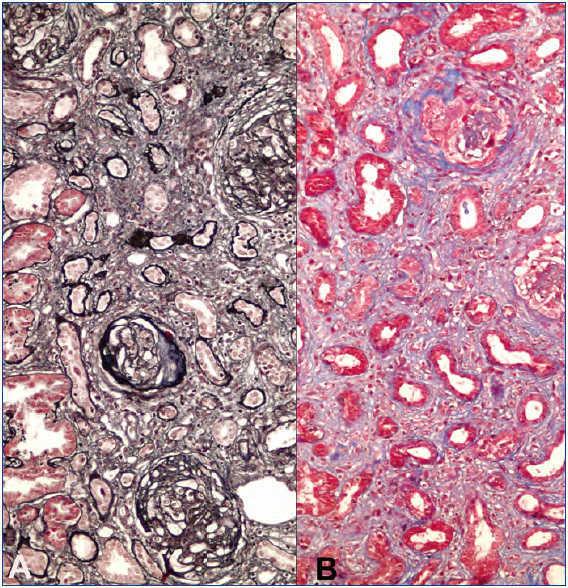

A 23-years-old non-smoker university student male patient presented with minimal bilateral edema in lower extremities that was present for two weeks. He had no gross hematuria, hemoptysis or other pulmonary symptoms. His past medical history was unremarkable. Laboratory evaluation revealed 7200mg/day proteinuria with normal renal functions (serum creatinine: 1mg/dL). Serum albumin level was 4g/dL. Urinalysis showed 3+ proteinuria with microscopic hematuria. Anti-nuclear and anti-double-stranded DNA antibodies, HIV, hepatitis B and hepatitis C serologies were negative. Complement levels were normal. Renal ultrasonography was normal. Renal biopsy was consistent with anti-GBM antibody disease with diffuse linear IgG staining along the GBM, diffuse endocapillary proliferation and cellular/fibrocellular crescent formation in 40% of glomeruli (Figure 1). Numerous glomeruli showed segmental scarring. As soon as the diagnosis was confirmed with positive anti-GBM antibody in serum, plasmapheresis and immunosuppressive treatment was started. Fourteen plasmapheresis sessions were performed until antibodies disappeared. After three days of intravenous pulse methylprednisolone treatment (500mg/day), he was maintained on oral prednisolone (started with 1mg/kg/day and tapered slowly) and monthly intravenous 750mg cyclophosphamide infusions. After twelve intravenous cyclophosphamide treatments, serum creatinine was 1.3mg/dL, albumin was 3.1g/dL and 24-h protein excretion was 4g/day. Thereafter he was maintained on low dose prednisolone (5mg/day) and azathioprine (100mg/day) combination. However under this treatment his renal functions deteriorated and a second biopsy had to be performed after 18 months when creatinine level increased to 2mg/dL and proteinuria to 6g/day. Although serum anti-GBM antibody and ANCA were negative at that time, histomorphologic examination demonstrated ongoing active disease with crescents, linear immunofluorescent staining for IgG on GBM’s and significant chronic injury (Figure 2). Pulse methylprednisolone followed by oral prednisolone, cyclosporine and mycophenolate mofetil could not prevent further deterioration of renal functions. Furthermore he suffered from a herpes-zoster infection and had to struggle with intracranial abscess caused by actinomyces. Immunosuppressive treatment was stopped and regular hemodialysis treatment was started on the 27th month after first diagnosis.

Figure 1. First renal biopsy from the patient.

Figure 2. Second kidney biopsy from the patient.